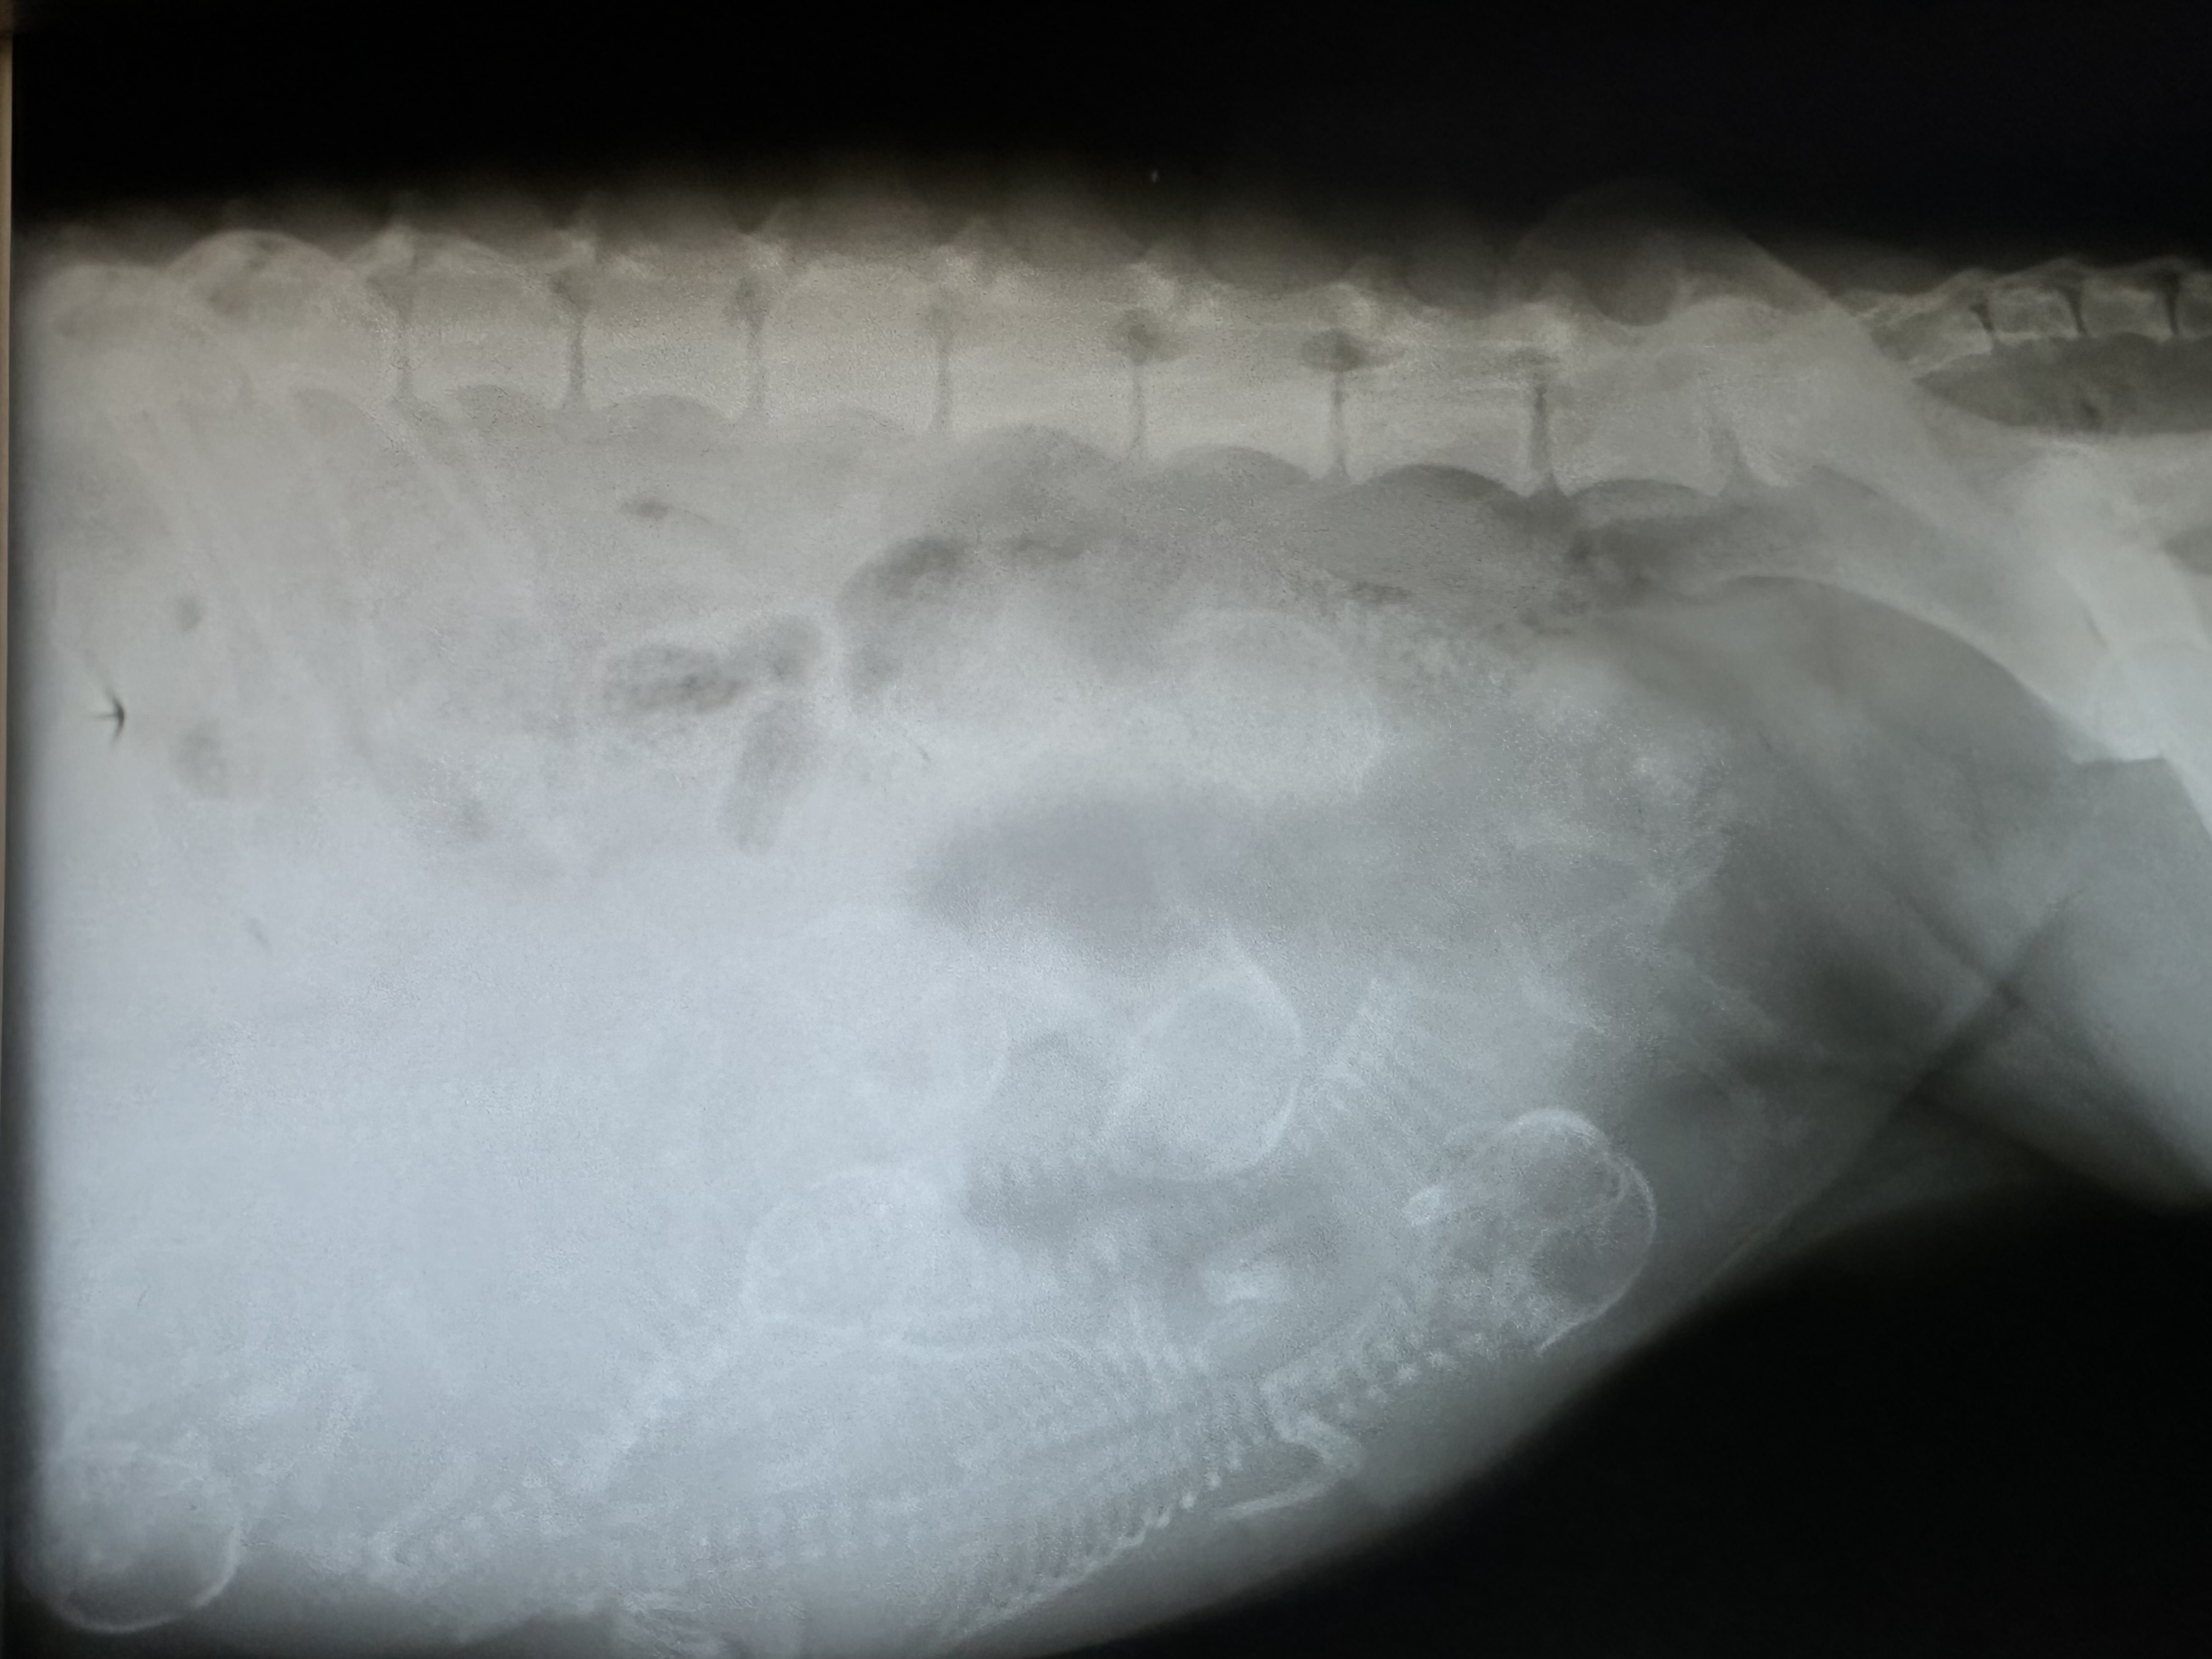

Heute ist bereits Tag 57 der Trächtigkeit. Masha hat knapp 5 Kg zugenommen und ein stattliches Bäuchlein bekommen. Von oben kaum zu sehen, ist es von der Seite unübersehbar. Die letzten Tage war sie dauerhungrig, was sich nun nach dem heutigen Röntgentermin auch erklärt.

Somit hoffen wir in den kommenden Tagen auf eine komplikationslose Geburt.